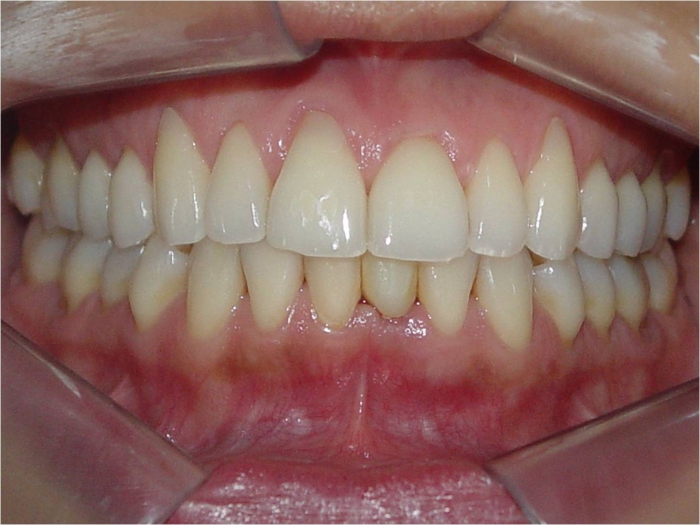

Imagens do dente provisório fixo imediato, no implante Cone Morse Facility